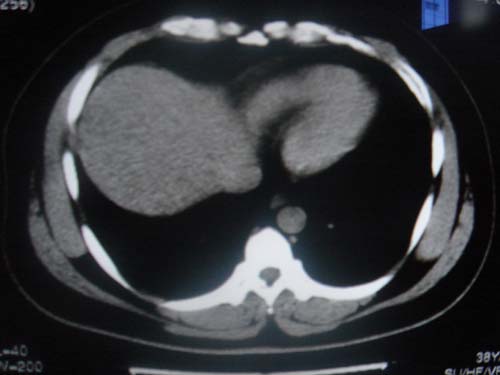

患者 男 40 右上腹不适 有胆囊息肉病史2年

最后二副图像示胆囊壁增厚,与肝分界欠清,建议强化ct或磁共振

片中示肝脏的ct值低于脾脏,肝脏右叶外缘部份凹凸不平,考虑脂肪肝,肝硬化可能。结合其检查如b超或ct增强检查。

肝右叶密度不均,脾大。强烈要求增强扫描除外浸润型肝癌。

肝大   密度降低  脾大  脂肪肝?